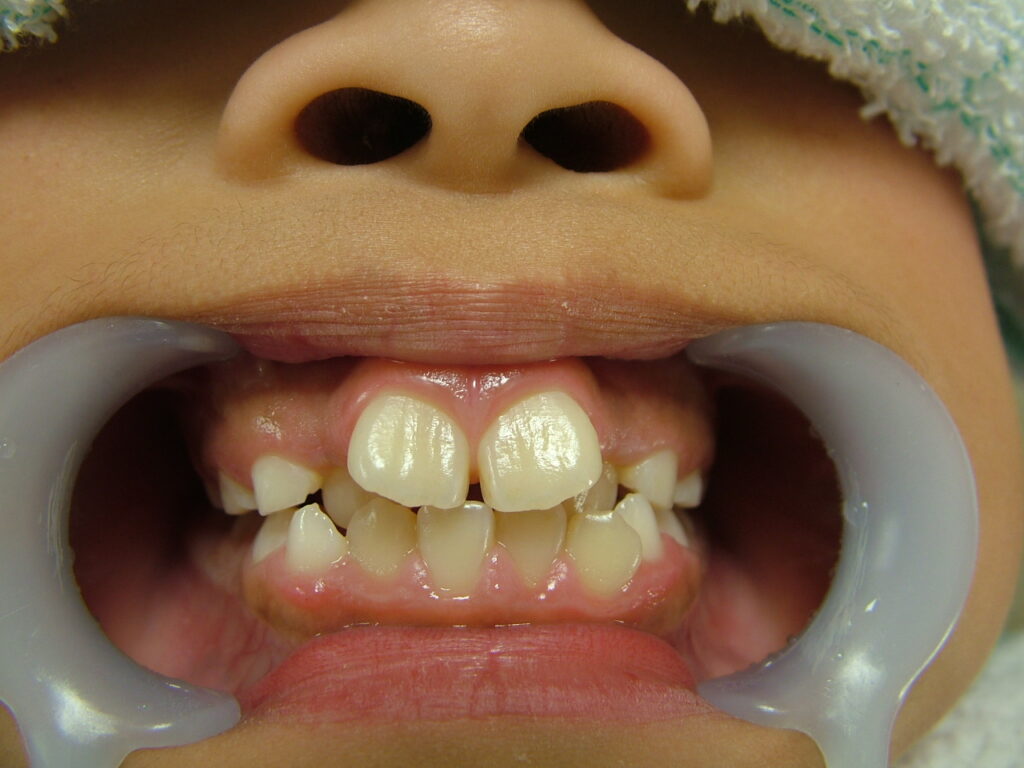

治療前

• 初診:2012年、9歳女児、

• 主訴:出っ歯と歯のがたがたが気になる。

• 診断:1級過蓋咬合、上下前歯叢生、上顎左右側切歯クロスバイト